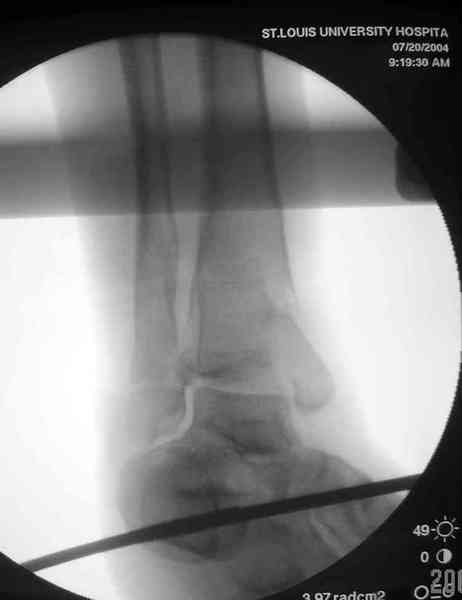

Дополнительные ренгенограммы после дистракции и

обязательная комьютерная томография дают возможности разузнать топографию расположения фрагментов, что немаловажно для планирования хирургического доступа.

По апексу фрагмента ориентируется при планировании

фиксации, также предоперационно определяется

направление фиксирующего материала: шурупа или спицы с упорной площадкой.

Здесь выставлена пара случаев перелома пилона, оба

случая леченные этапным наружным фиксатором.